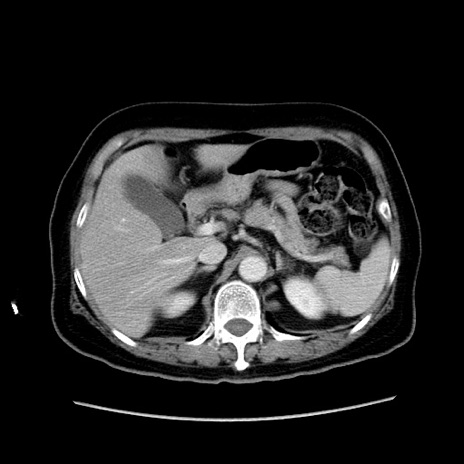

症例19(横断像)

【症例】80歳代女性

【主訴】下腹部痛

【現病歴】約8時間前より下腹部痛の出現あり、救急外来受診。

【既往歴】両側付属器切除

【身体所見】意識清明、下腹部正中に手術痕あり、その部位に一致して圧痛と反跳痛あり。腸蠕動音は亢進。

【データ】WBC 9300、CRP 0.15